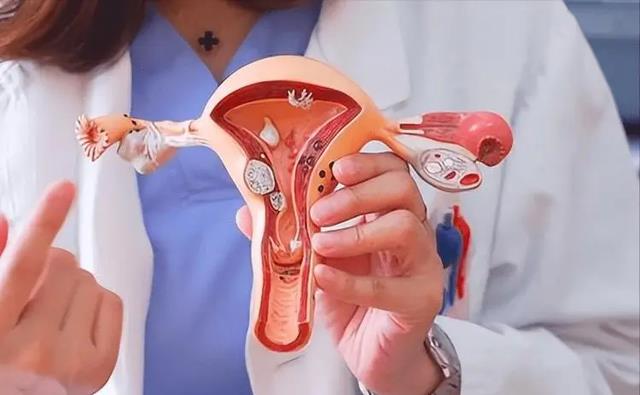

“上环”作为一种长效、经济、简便的避孕方式成为了许多女性的第一选择。那时,节育环的技术还不像现在这样成熟,种类和材质也相对单一。

长期“上环”可能会增加女性患上妇科炎症的风险,例如盆腔炎、宫颈炎等。这些炎症不仅会给女性带来身体上的痛苦,还可能影响到她们的生育能力。虽然目前医学界尚无定论,证明“上环”与子宫肌瘤之间存在直接的因果关系,但大量临床案例表明,长期“上环”的女性,患上子宫肌瘤的概率明显高于未“上环”的女性。

有些女性因为“上环”时间过长,节育环与子宫组织发生粘连的情况,这给取环手术带来了极大的难度和风险。在一些极端案例中,医生甚至需要切开子宫,才能将节育环取出,这无疑会对女性的身体造成更大的伤害。